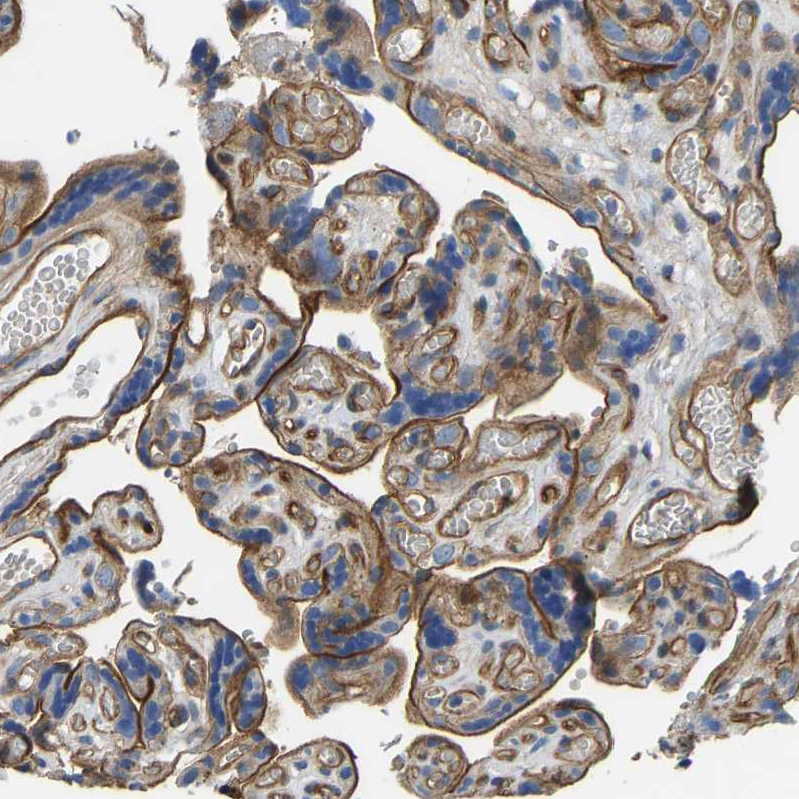

Immunohistochemical staining of human lung shows strong membranous positivity in pneumocytes.